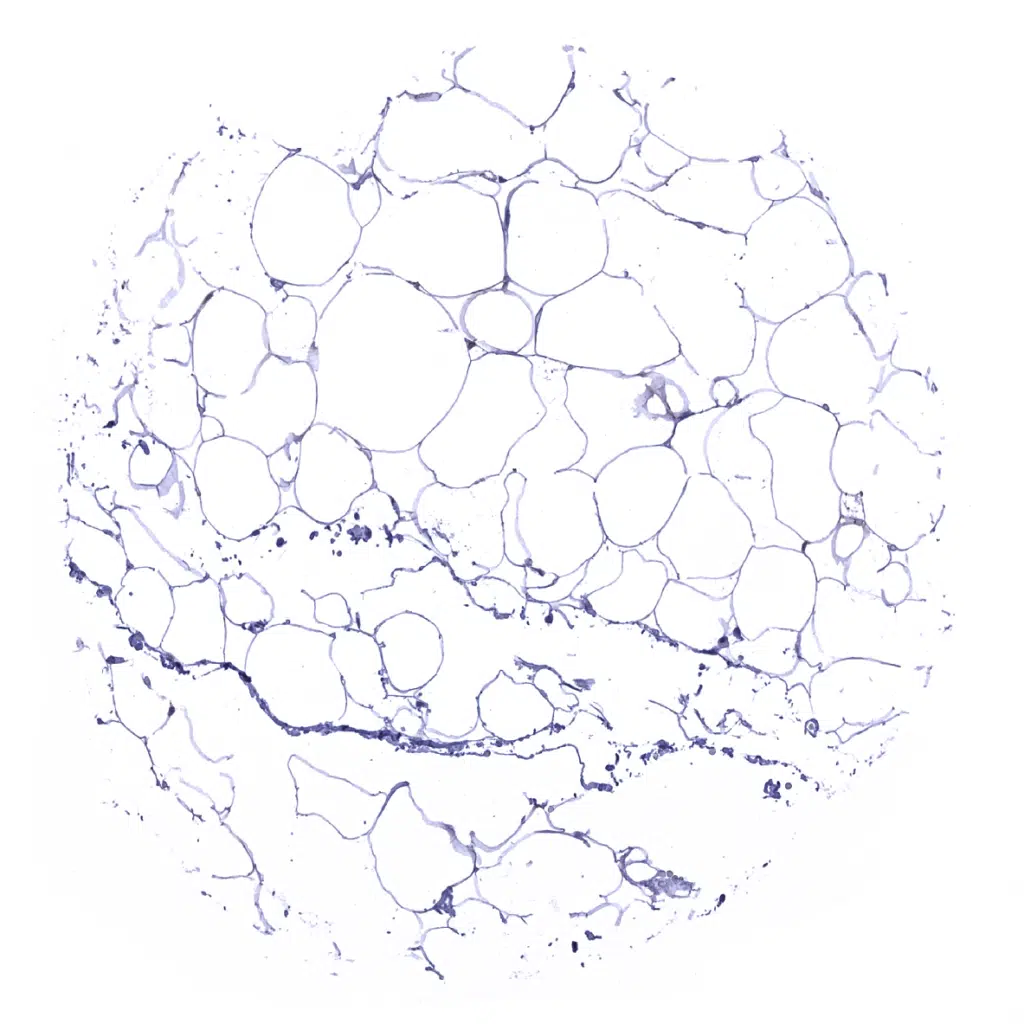

Fat

Parotid gland – Weak GS staining of excretory ducts but moderate to strong positivity of fat cells